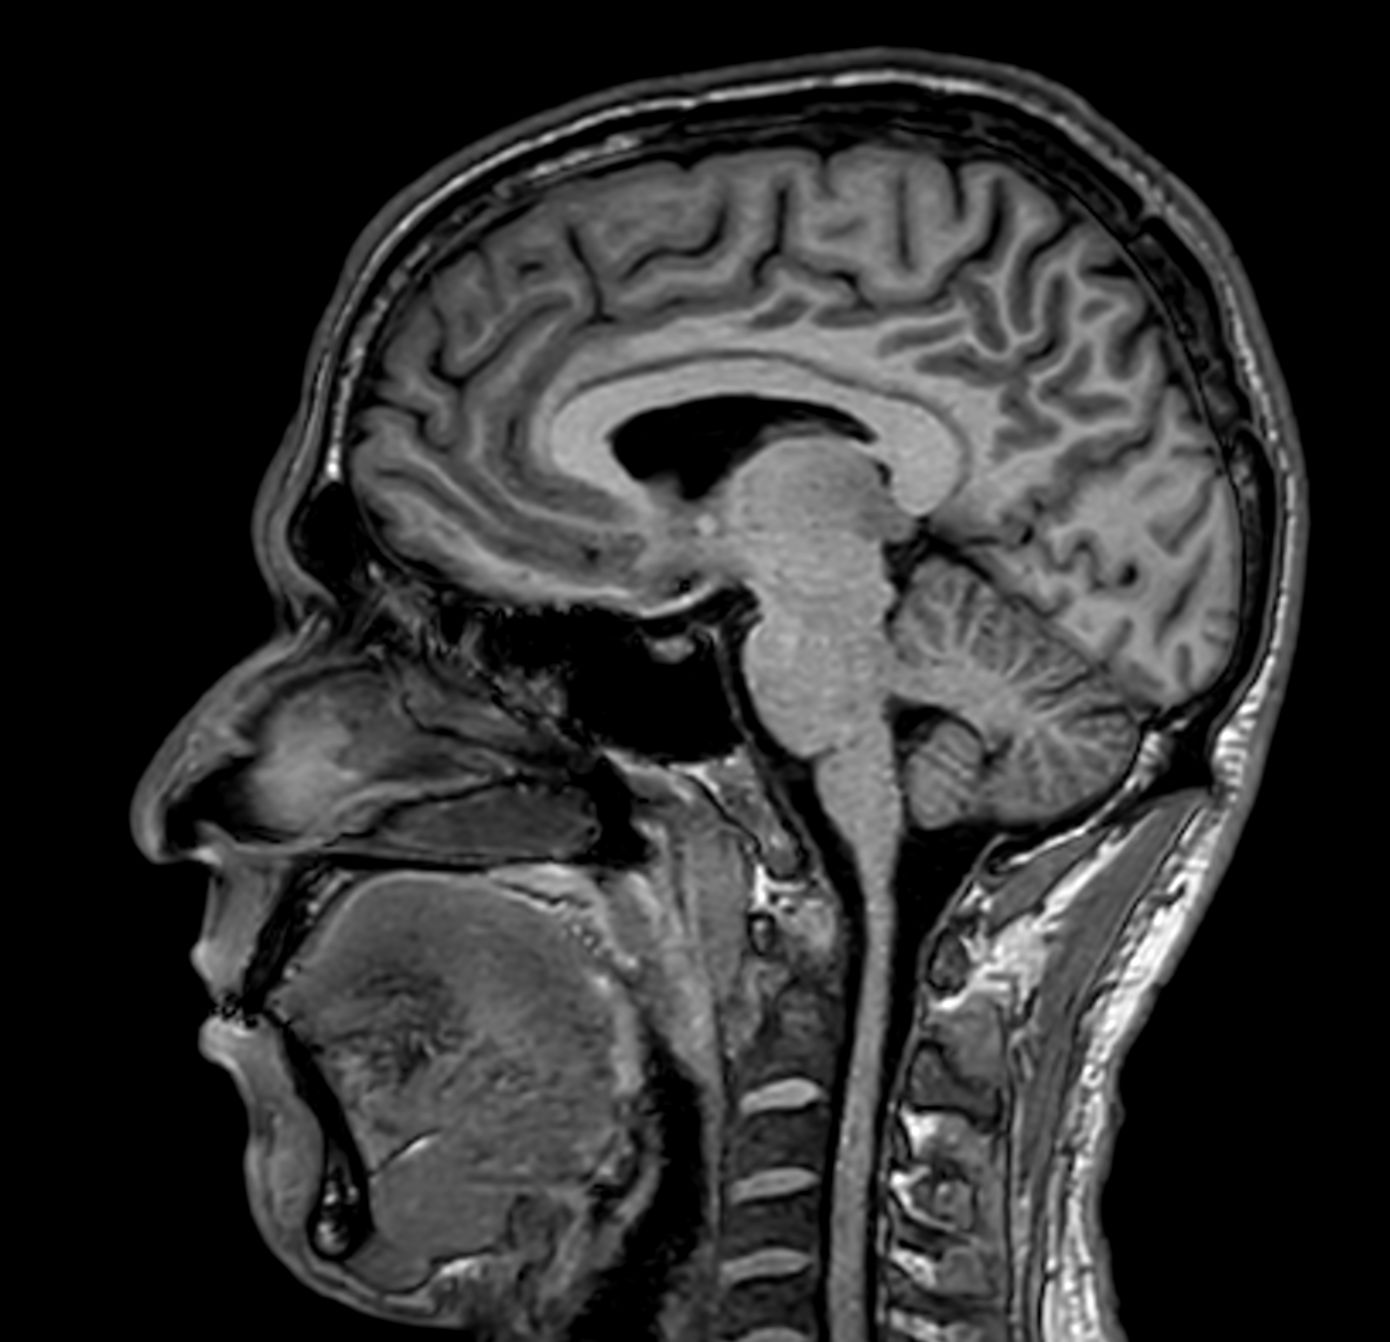

Alzheimer’s Disease Anti-Amyloid Immunotherapies (ARIA) 1.5T

Amyloid clearing medication, such as Aduhelm (Aducanumab) and Leqembi (Lecanemab) have been cleared by the FDA in 2022/2023, to slow down cognitive decline in early-stage Alzheimer’s disease. ASNR-recommendations for AD therapeutic imaging were published in 2022 for eligibility assessment as well as for monitoring for amyloid-related imaging abnormalities. This ExamCard includes ASNR-recommended consensus protocols for imaging of Alzheimer’s Disease Anti-Amyloid Immunotherapies (ARIA). (Cogswell et al., AJNR 2022,43(9)E19-E35;DOI: https://doi.org/10.3174/ajnr.A7586))